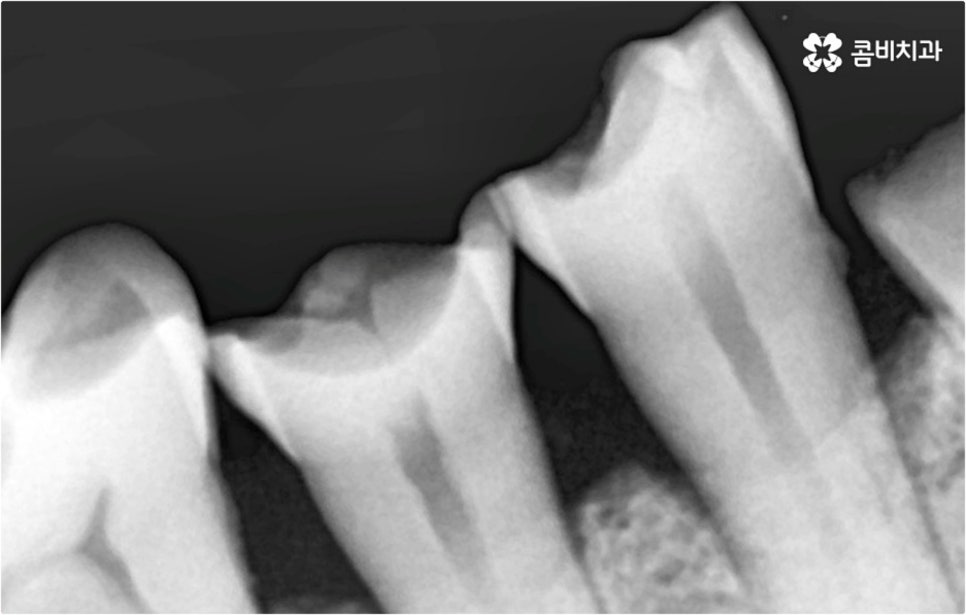

특히 한 두 개가 아니라 대부분의 치아를 잃게 되었을 때는 식사를 할 때 문제가 생겨 살아가는 데 필요한 영양소를 제대로 공급받지 못할 가능성이 높아질 뿐 아니라 장기적으로 소화 불량, 위장 장애 등을 겪을 수 있어요. 잘 씹지 못하면 치매에 걸릴 수 있다는 연구 결과도 있기 때문에 무심하게 넘어가시면 안 될 거예요. 또한 치아 상실을 오랜 시간 방치하면 잇몸뼈가 흡수되고 주변 치열이 쓰러지는 등 교합이 어긋날 수 있으며 얼굴 균형이 달라지는 등 심미적으로도 좋지 않은 영향을 받을 수 있어서 될 수 있는대로 빨리 이를 대체해 주실 필요가 있어요.

예를 들어 사고를 통해 한꺼번에 여러 개의 치아가 부러지거나 빠진 경우 연령 또는 전신 질환 여부 등을 살펴보고 치조골 상태가 양호하다면 보다 빠르고 간편한 당일 식립 방식을 이용해 볼 수 있어요. 그러나 하나 둘씩 치아가 빠질 때 마다 제때 치료를 해 주지 않아 치료 시기를 놓치고 결과적으로 무치악 상태에 이른지 오래 된 경우 또는 틀니를 오래 착용하여 잇몸뼈가 이미 많이 내려앉은 경우라면 바탕이 되는 잇몸뼈를 보충해 준 후 식립을 진행하는 방식을 이용해야 할 거예요.

아무 것도 없는 상태에서 제대로 저작 기능을 발휘할 수 있도록 다시 구강 내부를 재현하는 전악임플란트 는 굉장히 고난도에 속하는 치료이기 때문에 충분한 임상 경험을 가지고 있는 숙련된 의료진과 함께 하실 필요가 있어요. 전악임플란트 방식이 빠진 영구치 자리마다 다 임플란트를 식립하는 것이 아니라, 상하악 각각에 8~12개 정도로 필요한 최소한의 인공 치근을 심고 그 사이 사이는 브릿지 방식으로 보철물을 연결하는 것이기 때문에 저작력을 골고루 분담하여 안정적인 지속성을 높일 수 있도록 환자 개개인의 상태에 맞게 인공 치근의 위치, 각도, 간격, 심는 깊이 등을 세밀하게 설정하여 교합을 제대로 맞출 수 있는 시술자의 뛰어난 기술력과 풍부한 노하우가 요구되는 거예요.

임플란트 수술 후 발생할 수 있는 혹시모를 부작용 중 가장 대표적인 것은 주변 잇몸에 염증이 생기는 거예요. 임플란트 치아는 구조상 자연 치아와 다르게 자연스럽게 움직이면서 충격을 흡수하는 치주 인대가 없는 만큼 갑작스럽게 큰 힘이 가해질 수 있는 너무 딱딱한 음식을 씹으면 잇몸에 부담이 가서 피가 나거나 부어 오를 수 있으며, 주변 위생을 청결하게 유지하지 않으면 세균이 증식하여 염증이 생길 수 있으니 항상 잇몸 건강 상태를 양호하게 관리하는데 신경쓰실 필요가 있어요.